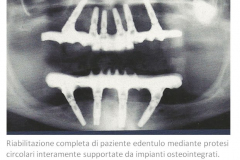

L’implantologia è una branca della Chirurgia Orale che si occupa della riabilitazione funzionale dei pazienti affetti da edentulismo totale o parziale tramite l’utilizzo di impianti dentali: dispositivi in titanio che, inseriti nell’osso mascellare o mandibolare, simulano per forma e funzione la radice naturale del dente permettendo la connessione di protesi, fisse o rimovibili, per il ripristino di una corretta funzionalità masticatoria e un’ adeguata estetica.

Per questo oggi l’’implantologia moderna è una disciplina largamente sperimentata ed efficace in grado di risolvere quasi tutti i problemi di edentulismo.

In alcune situazioni attentamente selezionate, inoltre, il protocollo protesico può prevedere un carico immediato , ovvero l’immediata protesizzazione degli impianti.